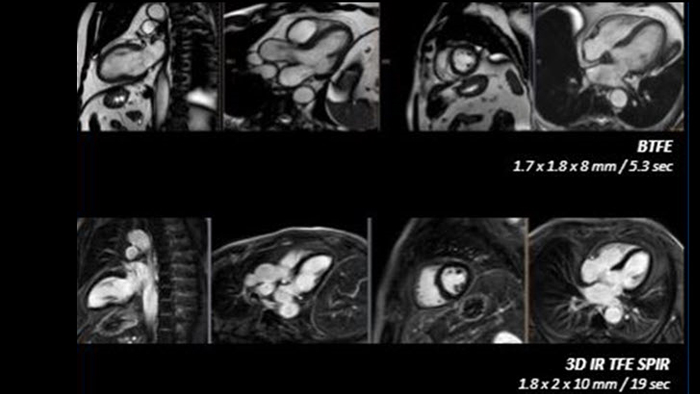

Nutzen Sie das volle Potenzial der MRT während des gesamten Behandlungspfades mit ultraschnellen Untersuchungen, einem optimierten Arbeitsablauf, hochwertiger diagnostischer Bildgebung und verbessertem Patientenkomfort.

Erhöhen Sie die Diagnosesicherheit und klinische Effizienz durch überlegene Bildqualität, moderne Quantifizierungsfunktionen und Automatisierungstechnologien.